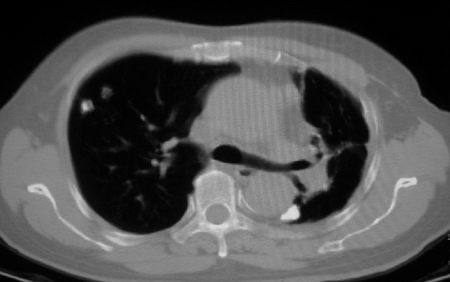

以下是引用李衡钧在2008-7-24 14:24:00的发言:[br]左侧胸廓变小,左肺上叶见大面积致密阴影,其内有空洞及不规则钙化。上纵隔略向左移位,上肺胸膜增厚。左肺门及纵隔淋巴结增大。右肺见散在的致密结节影。[br]印象:继发性肺结核。